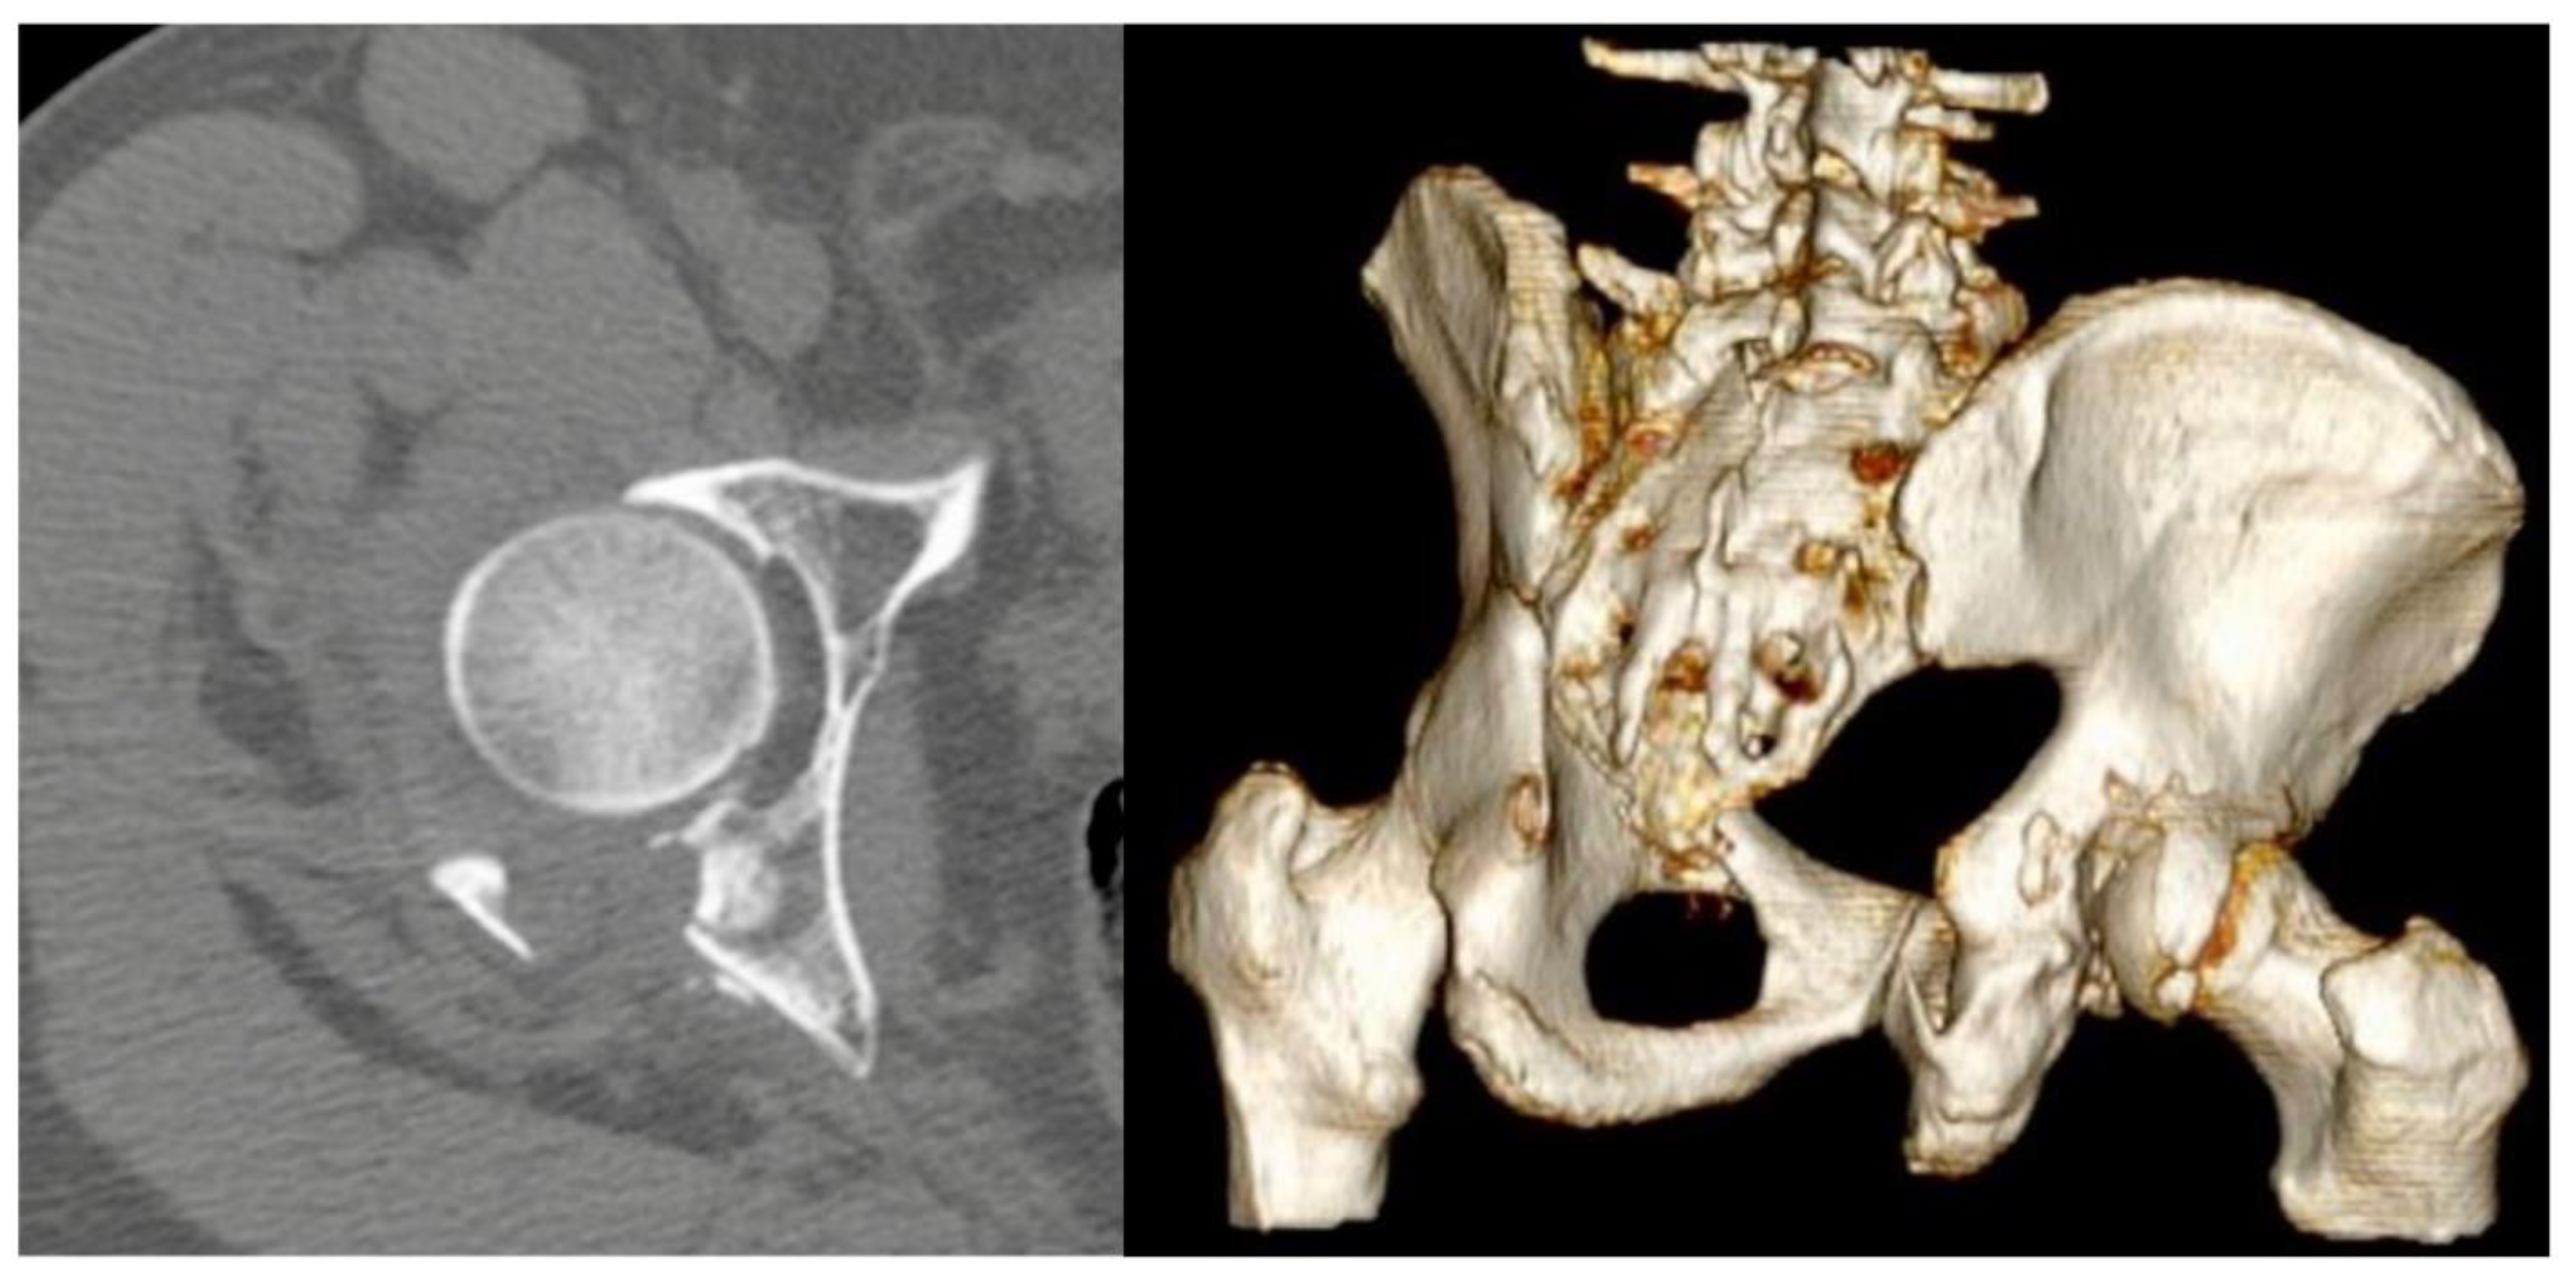

Spring Plates as a Valid Additional Fixation in Comminuted Posterior Wall Acetabular Fractures: A Retrospective Multicenter Study

2. Materials and Methods

3. Results